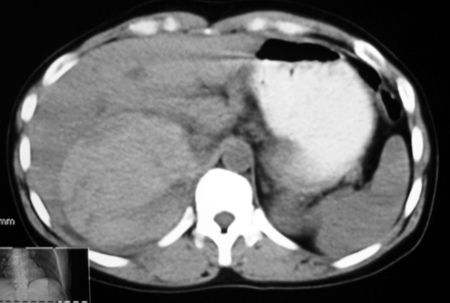

以下是引用bmw011在2009-4-23 13:28:00的发言:[br]考虑右肾包膜下血肿。

以下是引用卜一在2009-4-23 15:43:00的发言:[br]考虑右肾包膜下血肿,不排除占位病变伴出血可能,建议进一步检查。